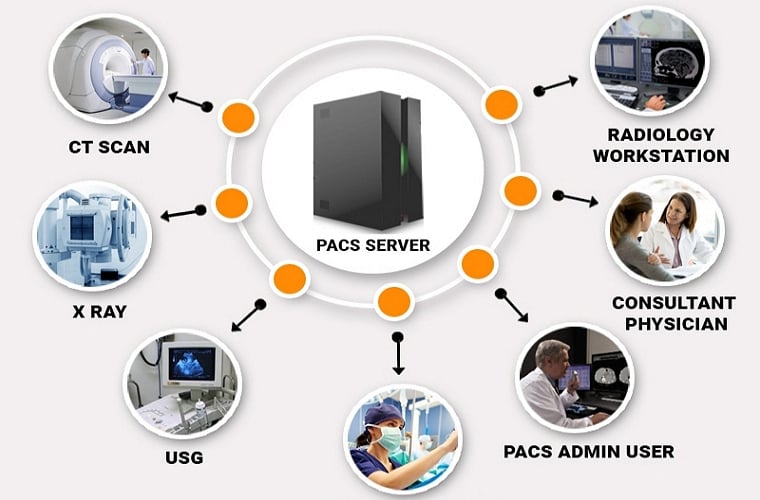

DICOM + PACS SERVER

The DICOM PACS Server is a medical imaging software designed to store, retrieve, and distribute medical images and associated data in compliance with the DICOM standard.

Our PACS Server provides a lightweight, open-source solution with features such as DICOM networking, anonymization, query/retrieve capabilities, and support for various medical imaging modalities like X-ray, MRI, CT scans, etc. It's highly customizable, scalable, and can be integrated with other healthcare IT systems, making it a popular choice for managing medical image archives.

DICOM PACS Servers/Clients Solutions are must for Big Hospitals or Radiology Diagnostic Imaging Centers. We are building Cloud based Radiology Diagnostic Imaging Centers.

Multi Modalities

Supports All Modalities

X-Ray, CT, MR, ULS, RF, PET, Dental, Fundus, OCT

Integration

- DICOM Viewer.

- Vol Rendering Plugin.

- Worklist Plugin.